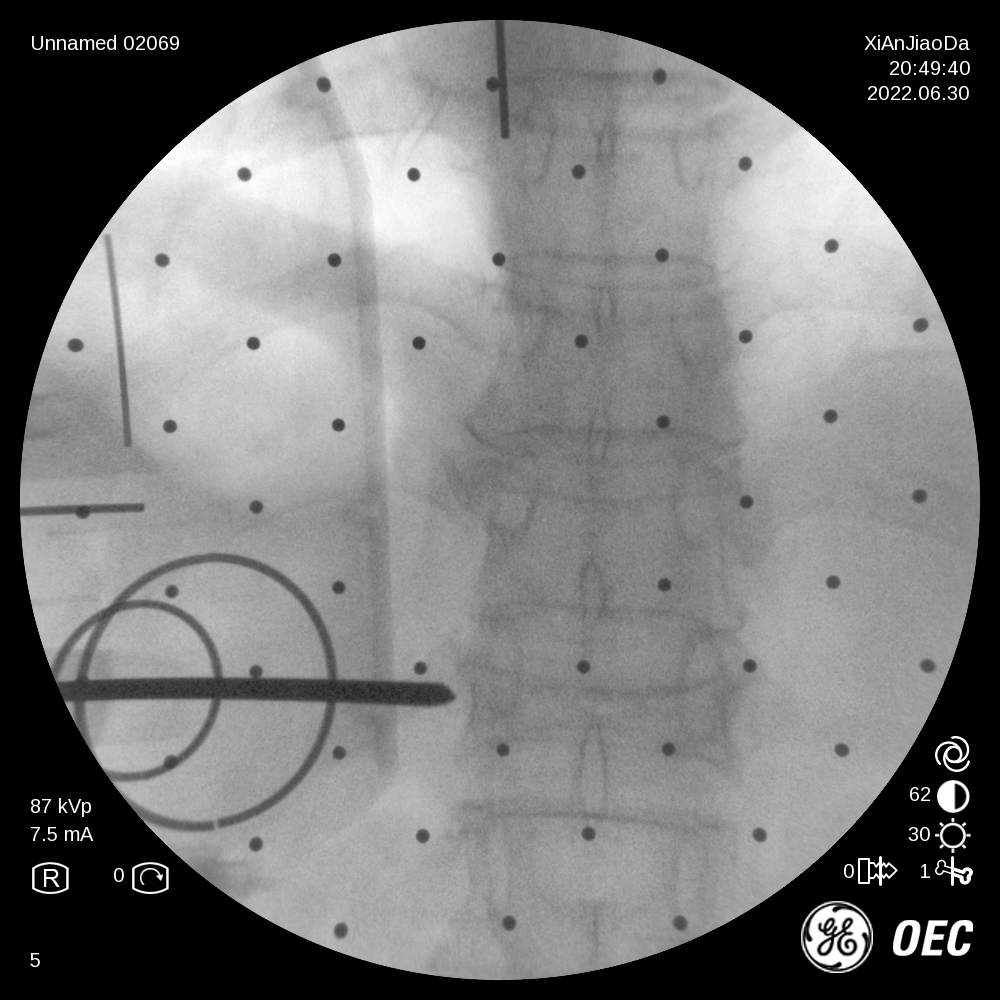

在该机器人辅助手术过程中,仅需通过正侧位进行伤椎识别,通过软件将正侧位透视图与术前规划数据的结合,即可得到病人伤椎的姿态以及实际的穿刺角度,之后机械臂根据软件参数进行精准定位,手术医生在机械臂引导下一次性进针成功,并对进针位置角度表示满意,整个过程少于20分钟,实现了手术的更精准化、高效化。相较于传统定位流程,术前规划只能保存在医生脑海中,术前与术中流程无法很好的衔接,术中穿刺依赖医生丰富的经验,对于情况复杂的病人,术中需要反复试验,导致手术时间延长、患者受辐射量增加。后续放置球囊、注入骨水泥等操作则同传统手工操作。